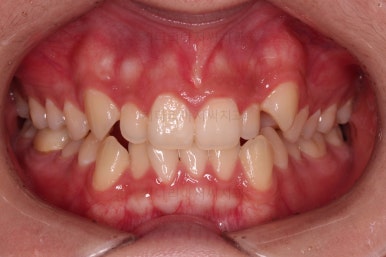

마찬가지로 초진 시 입안의 모습인데요.

위아래 앞니가 삐뚤고, 송곳니는 덧니처럼 불룩 튀어나가 있네요.

위아래 앞니는 안으로 굽어 들어와 있는 옥니(뻐드렁니 반대) 양상이었고요.

그리고 마무리 때 디테일에 문제가 생길 수 있는 부분인데, 윗니 대문니(가장 중간 치아)와 송곳니 사이의 치아를 작은 앞니라고 하는데요.

이 작은 앞니가 가져야 될 크기보다 더 작은 양상이었습니다.

이런 치아를 왜소치라교 표현합니다.